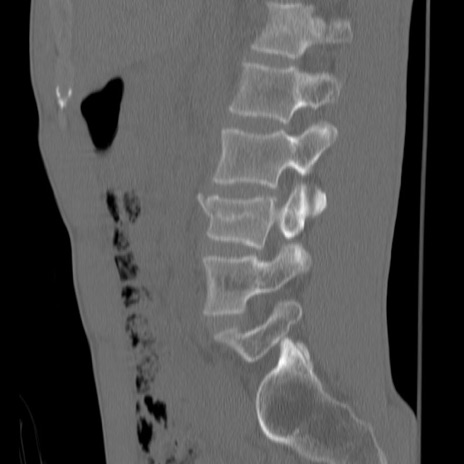

症例3 腰椎CT(矢状断像)

腰椎CT

3D再構成